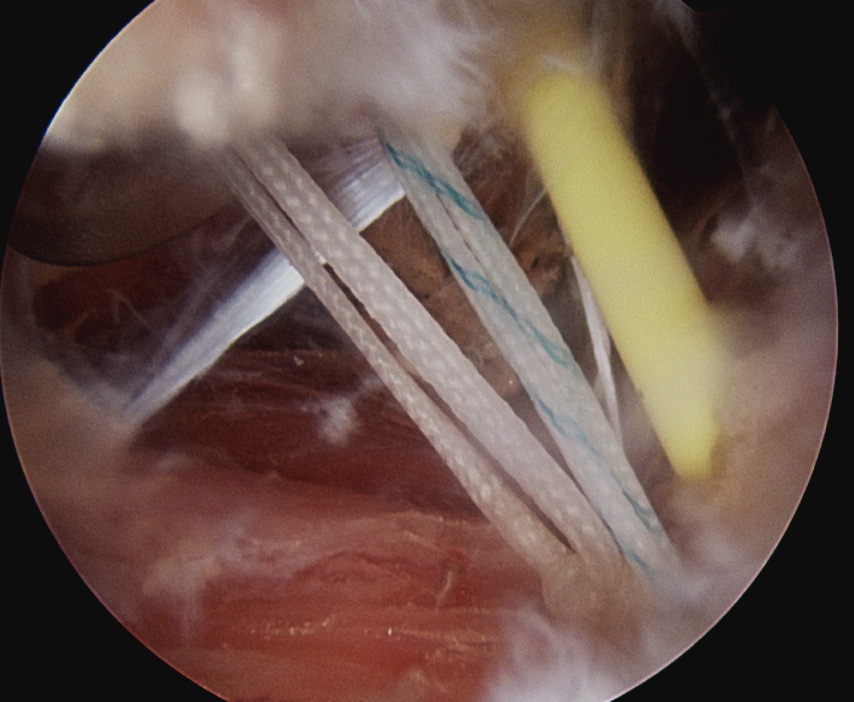

- insert anchors at medial aspect of defect

- suture passer / birds beak to take bite of capsule

Anchor insertion into Hill Sachs lesion